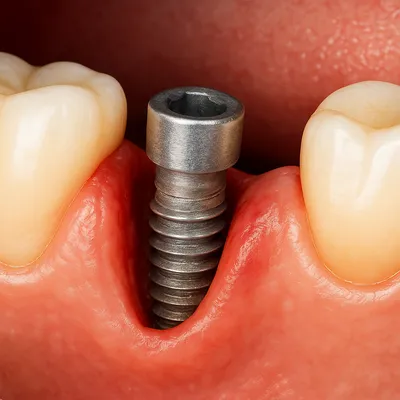

تأثیر تحلیل لثه بر ایمپلنت یا درمانهای مجاور

وقتی تحلیل لثه دندان روکش شده در مجاورت ایمپلنت یا بریج رخ میدهد، سلامت این درمانها نیز به خطر میافتد. عقبرفتگی لثه باعث میشود حاشیه ایمپلنت یا پایههای بریج در معرض تجمع پلاک و باکتری قرار گیرد و خطر التهاب لثه یا حتی عفونت لثه افزایش یابد.

در چنین شرایطی احتمال تحلیل استخوان فک نیز بیشتر میشود و استحکام ایمپلنت کاهش مییابد. از طرف دیگر، تغییر خط لثه میتواند زیبایی لبخند را هم تحت تأثیر قرار دهد و باعث نامتقارن دیده شدن روکش یا بریج شود.

بنابراین در بیماران دارای درمانهای ترکیبی، تشخیص زودهنگام و کنترل تحلیل لثه دندان روکش شده اهمیت بیشتری دارد تا از آسیب به ایمپلنت و سایر دندانهای ترمیمشده جلوگیری شود.